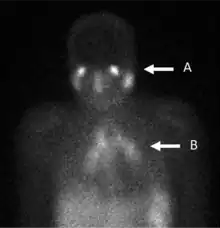

La scintigraphie au gallium est un type de test de médecine nucléaire utilisant un gallium-67 (67Ga) ou gallium-68 (68Ga) radio-pharmaceutique pour obtenir des images d'un type spécifique de tissu, ou l'état de maladie tissulaire. Les sels de gallium peuvent être utilisés comme citrate de gallium et nitrate de gallium. La forme de sel n'est pas importante, car c'est l'ion de gallium libre dissous Ga3+ qui est actif[1]. Les sels 67Ga et 68Ga ont des mécanismes de captage similaires[2]. Le gallium peut également être utilisé sous d'autres formes, par exemple 68Ga-PSMA est utilisé pour l'imagerie du cancer de prostate. L'émission gamma de gallium-67 est détectée par une caméra gamma, tandis que l'émission de positons de gallium-68 est détectée par tomographie par émission de positons (PET).

Les sels de gallium sont absorbés par les tumeurs, l'inflammation et les infections aiguës et chroniques[3],[4] permettant l'imagerie de ces processus pathologiques. Le gallium est extrêmement utile pour l'imagerie de l'ostéomyélite impliquant la colonne vertébrale et pour l'imagerie d'infections plus anciennes et chroniques pouvant être à l'origine d'une fièvre d'origine inconnue[5],[6].